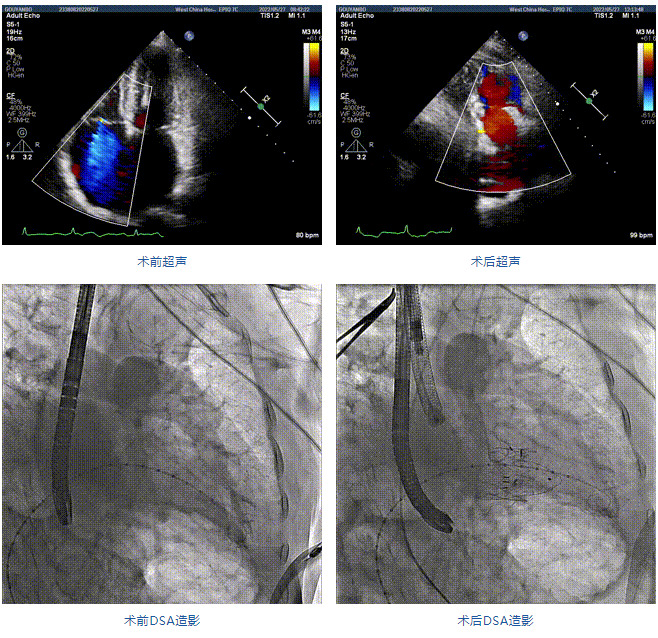

2022年5月27日,四川大學(xué)華西醫(yī)院心臟內(nèi)科陳茂、馮沅教授帶領(lǐng)的瓣膜病介入治療多學(xué)科團(tuán)隊(duì),在國內(nèi)首次采用純介入方式通過穿刺右側(cè)頸靜脈成功完成經(jīng)導(dǎo)管三尖瓣置換。植入的人工瓣膜是具有中國自主知識產(chǎn)權(quán)的LuX-Valve Plus系統(tǒng)。術(shù)中上海長海醫(yī)院陸方林教授和喬帆副教授給予了在線支持。

患者為89歲高齡男性,罹患三尖瓣反流多年,近期癥狀明顯加重,經(jīng)過充分的藥物治療后仍然存在嚴(yán)重心力衰竭。通過純介入方式實(shí)施三尖瓣置換,使這位超高齡的老人以最小的代價獲得了有效的治療。介入治療的效果十分滿意,術(shù)后三尖瓣反流消除,老人迅速恢復(fù),心功能明顯改善。該手術(shù)的成功實(shí)施標(biāo)志著國內(nèi)經(jīng)導(dǎo)管三尖瓣置換進(jìn)入純介入時代。

89歲男性。術(shù)前超聲報告顯示:雙房增大,左室壁肥厚,主、肺動脈增寬,三尖瓣重度反流。

團(tuán)隊(duì)前期經(jīng)過多次討論,制定了周密的手術(shù)策略和預(yù)案。由于患者已是近九旬的超高齡老人,傳統(tǒng)外科開胸手術(shù)風(fēng)險極高,純介入經(jīng)血管三尖瓣替換能夠明顯減少創(chuàng)傷。術(shù)中陳茂及馮沅教授結(jié)合體表定位在造影指示下精準(zhǔn)穿刺右側(cè)頸靜脈并預(yù)置兩把血管縫合器。成功建立經(jīng)皮血管入路后在食道超聲和DSA的引導(dǎo)下順利完成人工瓣膜植入,術(shù)后超聲和造影顯示人工三尖瓣同軸性良好,瓣架固定牢靠,無反流和瓣周漏,平均跨瓣壓差降為1mmHg。術(shù)畢收緊預(yù)置的血管縫合器縫線完成止血,縫合效果滿意,在手術(shù)室即刻拔除氣管插管。